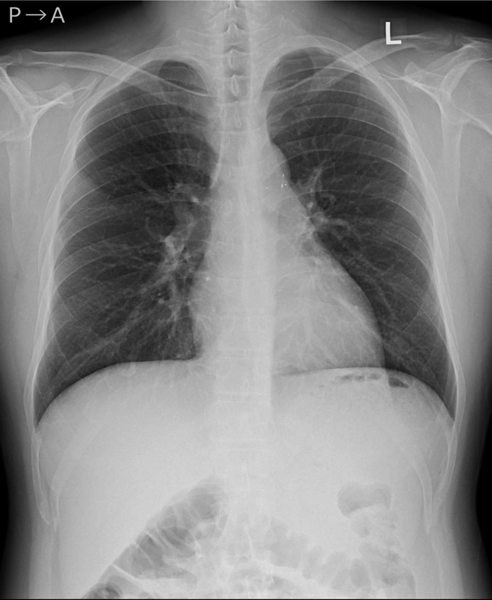

左→右短絡によるQp/Qsは1.2と推定され,心臓カテーテル検査の方針となった.身長168.6 cm,体重71.8 kg,血圧120/66 mmHg,脈拍数76回/分,経皮的酸素飽和度97%,浮腫なし,心拍整,第二肋間胸骨左縁Levine I/VI continuous murmur, bounding pulseなし,呼吸音清,腹部平坦軟,肝脾触知しない.入院時の胸部X線では心胸郭比(CTR : cardio thoracic ratio)47%と心拡大は軽度で,肺血管陰影の増強を認めなかった(Fig. 1).12誘導心電図は洞調律で心拍数60回/分,QRS軸-30°,有意な異常所見は認めなかった(Fig. 2).血液検査では,白血球9,700/µL, AST 28 U/L, ALT 36 U/L, NT-proBNP< 10 pg/mL, LDH 206 U/L, CPK 86 U/Lであった(Table 1).心エコー検査では肺動脈内連続性短絡血流があり(Fig. 3),収縮期max vel=3.7 m/sec拡張期max vel=2.9 m/secであった.また,軽度の僧帽弁逆流を認めた.左室駆出分画73%,左室流入波形(E/A=2.2 E/E′=6.9)と左室機能は保たれていた.明らかな下行大動脈の拡張期逆行性血流は認めなかった.心臓カテーテル検査では,下行大動脈からの造影でPDAはKrichenko A型(Fig. 4)に描出され,ampulla径3.5 mm, PA側2.2 mm,最狭部2.5 mm,長さ8.9 mmであった.Fick法を用いて計算したQp/Qsは1.0,肺血管抵抗値は1.08 Wood単位・m2であった.成人先天性心疾患診療ガイドライン4)に基づき,推奨クラスI,エビデンスレベルCと判断し,初回治療後34年目に再閉鎖目的で入院となった.

Fig. 1 Chest X-ray on admission

Cardiothoracic ratio was 47% without pulmonary congestion.